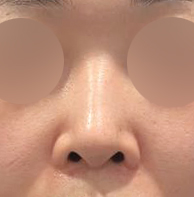

실리콘, 비중격, 귀연골, 기증늑연골사용해서

수술했고 이물질제거와 복코, 용코교정한지

3주차 됐는데요

벌써부터 너무 자연스럽고

평소 고민이었던 용코도 정말 많이 교정되고

자연스럽고 화려한 코라인이 나와서